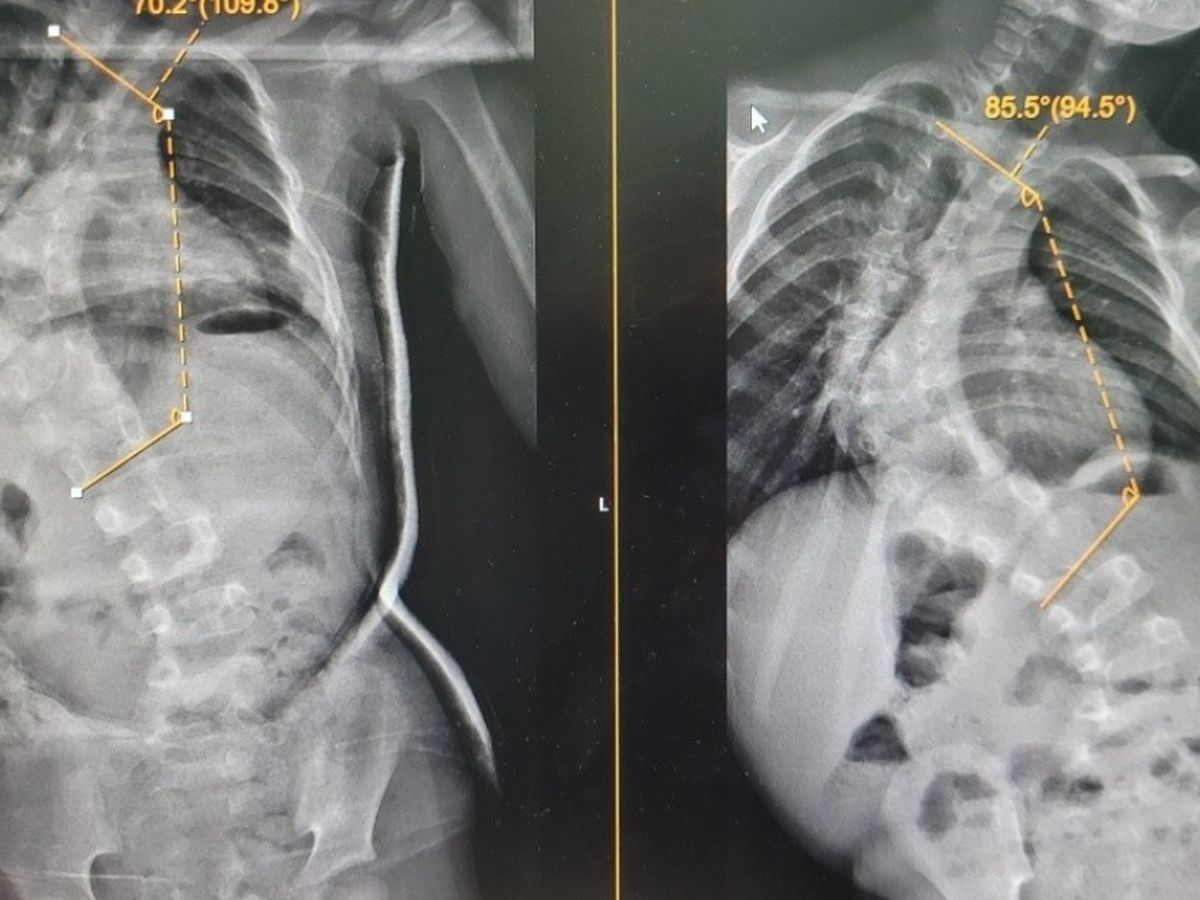

My little 6 year old daughter is having major spinal surgery on the 14th Feb. Violet suffers from serve scoliosis. She will be in hospital for up to two weeks.